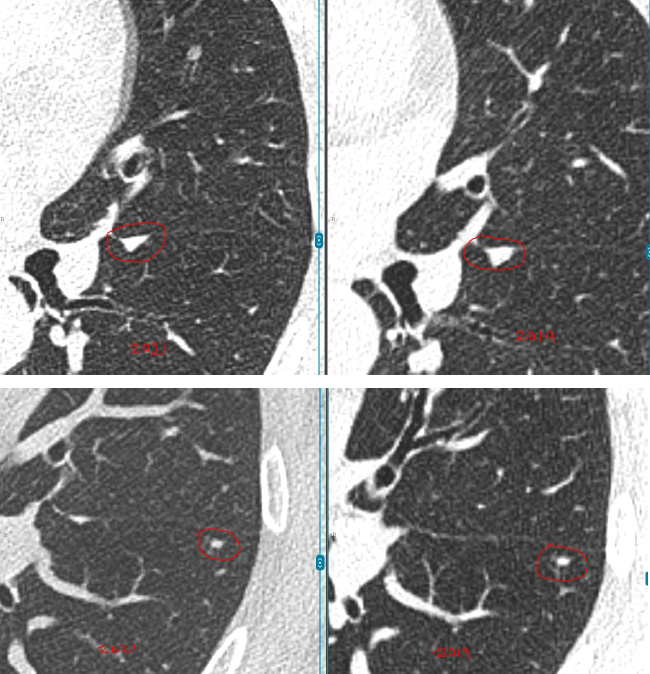

数年前,孙女士(化名)在一次体检中意外查出双肺多发结节:

左肺下叶:2枚实性结节,约5mm、3mm

右肺上叶:1枚磨玻璃结节,约4mm

每年复查,她都紧张得睡不着。好在3个结节都一直很“老实”,没变大。可四年后的一次CT复查,让她的心又提了起来:

左肺结节无变化,但右肺的4mm结节密度增高了,还又新添了一颗3mm的磨玻璃结节。

教授指出,右肺那颗4mm的磨玻璃结节虽然密度略有增加,但变化非常小,还不足以判断为恶化。

而左肺的两枚实性结节稳定了三年多,良性可能性超过99%。另外舌叶可见线状影,较前稳定,符合炎性、瘢痕特征。

至于新出现的那颗3mm磨玻璃结节,教授认为它也很“温和”,更像是一种暂时的炎性反应,有可能过段时间就自行消失了。

“这些结节都太小,目前还不到该切的程度,继续观察很安全。”L教授说。他建议孙女士每年复查一次CT,不需要手术、不用活检。